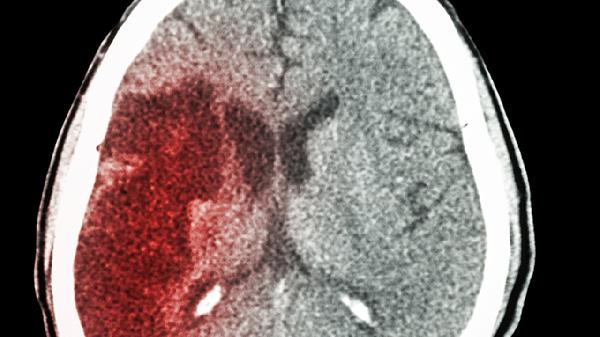

存在活动性消化道溃疡、严重肝肾功能不全或近期颅内出血史的患者禁用阿司匹林肠溶片。对阿司匹林过敏者可能出现哮喘发作或皮疹,需改用氯吡格雷片等替代药物。拟行外科手术前通常需停药7-10天,具体需由神经内科医生评估后决定。部分患者服用后可能出现胃部不适,可与质子泵抑制剂如奥美拉唑肠溶胶囊联用。